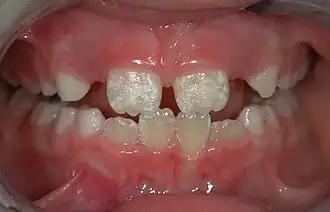

Irreversible enamel defects caused by an untreated celiac disease. They may be the only clue to its diagnosis, even in absence of gastrointestinal symptoms, but are often confused with fluorosis, tetracycline discoloration, or other causes.[50][51][52] The National Institutes of Health include a dental exam in the diagnostic protocol of celiac disease.[50]

There are 14 different types of amelogenesis imperfecta.[3] The hypocalcification type, which is the most common, is an autosomal dominant condition that results in enamel that is not completely mineralized.[53] Consequently, enamel easily flakes off the teeth, which appear yellow because of the revealed dentin. The hypoplastic type is X-linked and results in normal enamel that appears in too little quantity, having the same effect as the most common type.[53]